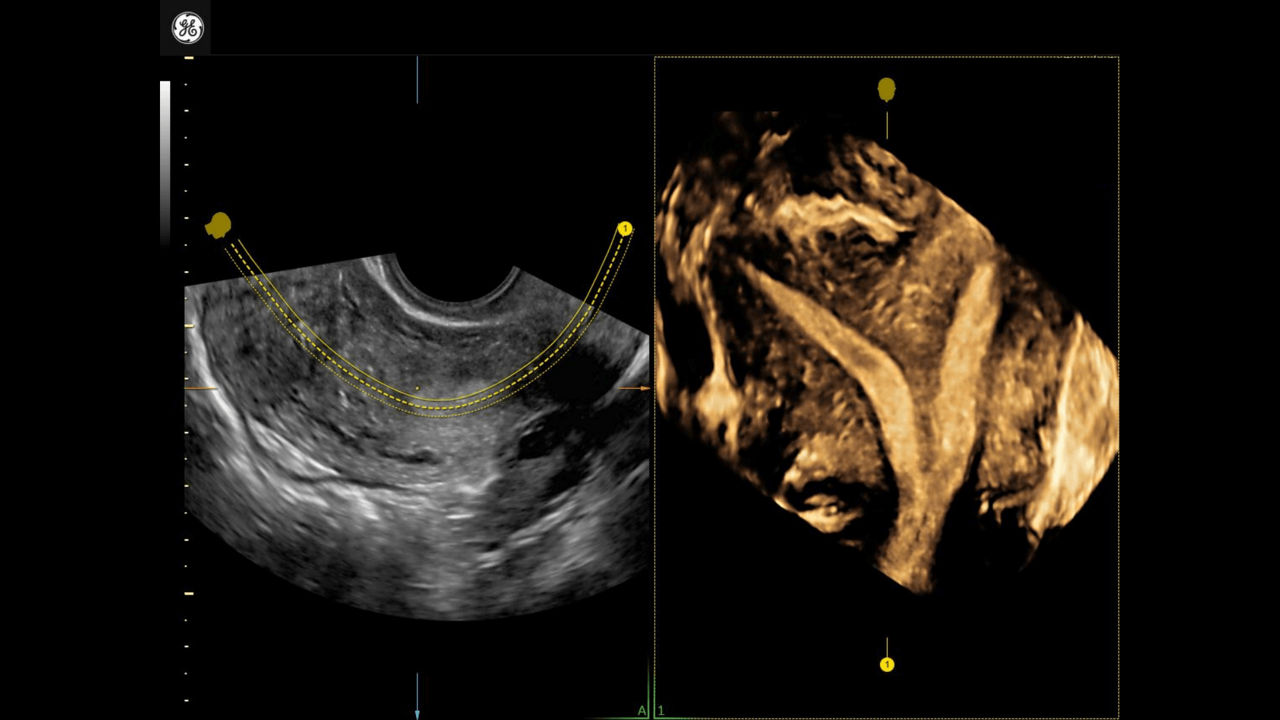

SonoLyst

AI tool helps automatically identify fetal anatomy.

Developed by: GE HealthCare - Voluson™

1_SonoLyst-Clinical-Image